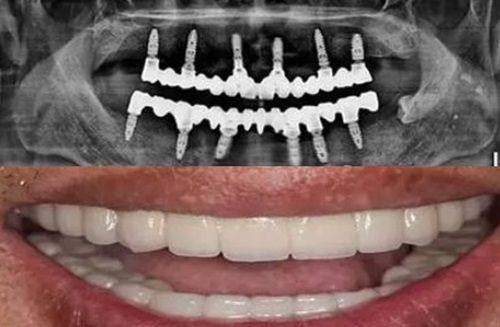

长期的发展也让医院在技术和设备方面不断更新和完善。和仁堂口腔引进了精良的口腔检查和矫正设备,能够更正确地诊断牙齿问题和进行矫正治疗。而且,医院的医生和护士也会定期参加培训和学习,不断提升自己的专精水平。这就确保了顾客能够享受到起初进、更专精的口腔医疗服务。

关于金属托槽矫正的收费,银川和仁堂口腔还是比较合理的。从收集到的资讯来看,传统金属托槽矫正价格大致在5800元起,金属自锁托槽矫正价格在9500 - 13800元左右,美国3M金属自锁矫正价格16000元起。不过,这些价格主要作为参考,具体价格还需要根据到院情况而定。在我进行矫正之前,李医生详细地给我介绍了不同类型金属托槽矫正的价格和特点,让我根据自己的经济情况和需求进行选择。